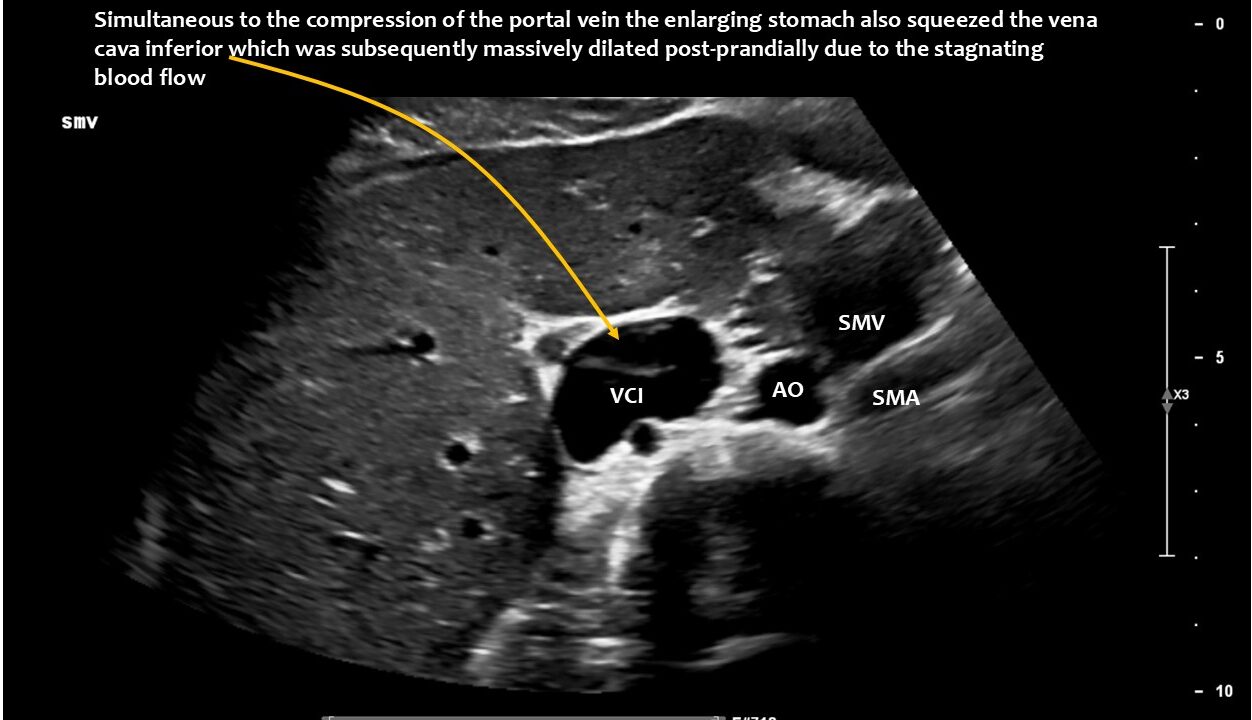

The enlarging stomach shifted the liver against the retrohepatic portion of the vena cava inferior contributing to pain after a meal in the lower abdomen.

- Pressing the liver against the vena cava inferior creating an additional pain in the right lower abdomen after a meal.

Postprandial compression of the vena cava contributed to eating difficulties due to pain caused by obstructed venous return from the abdomen to the heart.

The volume of food ingested and the associated enlargement of the stomach now led to a critical situation: the stomach pushed the hepatic artery (arteria hepatica communis), which runs along the underside of the liver, against the portal vein (vena portae), which carries blood from the spleen and intestines to the liver. This compressed the portal vein and caused blood to accumulate in the splenic vein (Vena lienalis/Vena splenica) and, above all, in the superior mesenteric vein. While the splenic vein runs parallel to the pars horizontalis duodeni, the superior mesenteric vein cuts across the duodenum at a right angle, similar to the superior mesenteric artery. The congestion of the superior mesenteric vein led to compression of the duodenum, even though there was sufficient space between the superior mesenteric artery and the duodenum. However, after food intake, the superior mesenteric artery shifted far to the left and thus no longer formed a clamp with the aorta for the duodenum. The swelling of the superior mesenteric vein, which is supplied with significantly more blood after food intake than when fasting in order to transport food components to the liver, was so severe as a result of the compression of the portal vein that food could no longer pass through the pars horizontalis duodeni. The clinical consequences for the patient were increasing nausea after eating due to the considerable distension of the pars descendens duodeni, rapid satiety, impaired food transport from the stomach despite lively peristaltic contractions of the stomach (misinterpreted elsewhere as gastroparesis), vomiting and significant weight loss. Even feeding via a percutaneous jejunal tube and a gastric tube could not stop the weight loss.